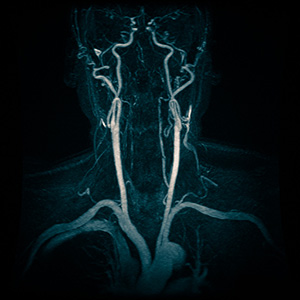

- Ангиография. Этот метод выявляет повреждения сосудов или новообразования на их стенках.

- УЗИ с допплерографией. Данный подход помогает определить наличие сужений и непроходимости в кровеносных сосудах.

- Магнитно-резонансная томография (МРТ). Дает возможность визуализировать патологии сосудистой сети головного мозга.